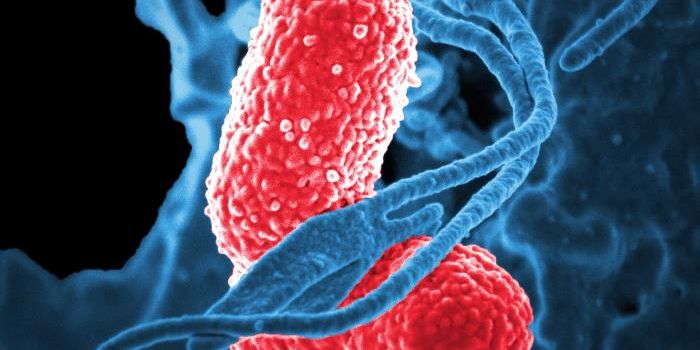

SEP 05, 2024Cell & Molecular BiologyCorynebacterium matruchotii ia a common bacterium that lives in human dental plaque; a colony is seen in this image by S ...

AUG 26, 2024Clinical & Molecular DXA colorized scanning electron micrograph depicts a Kupffer cell. / Credit: Thomas Deerinck, National Center for Microsco ...

AUG 07, 2024Clinical & Molecular DXKlebsiella pneumoniae (K. pneumoniae) is a common Gram-negative bacterium. They can live almost anywhere, including wate ...